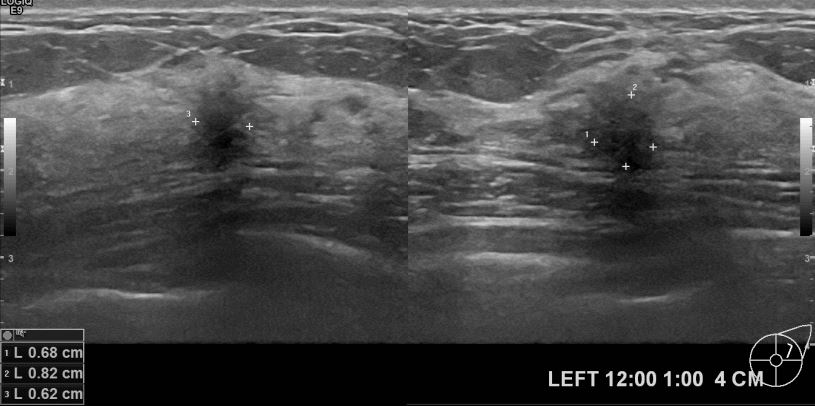

아산유외과 개원후 601번째 유방암 진단

외부검사상 이상소견으로 내원하신 40대 여성분으로 좌측유방 의심스러운 혹 조직검사시행해

유방암 진단되었읍니다.